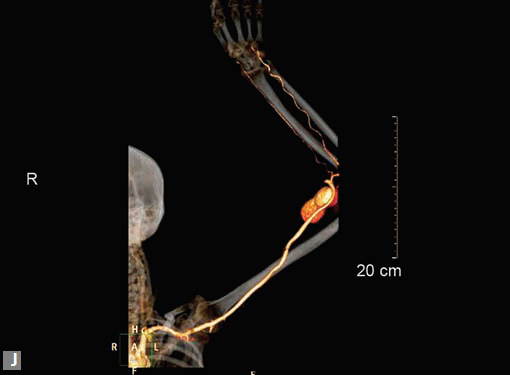

Figs 19A to Y (A to C) Scannogram (A), plain (B) and contrast study (C) show partial anomalous pulmonary venous connection; (D to F) Heterotaxy; (G) Aortic occlusion; (H and I) Aortic stents; (J) Aortic dissection with ‘Benz’ sign due to second dissection within the true lumen; (K, L and M) Aortic dissection with thrombus in pseudolumen following catheter angiogram; (N) Aortic dissection involving common carotid arteries and subclavian artery; (O, P, Q and R) Aortic dissection with right renal artery arising from true lumen and left renal artery from false lumen; (S, T, U and V) Stanford B dissection with extension Y to iliac vessels; (W to Y) Aneurysmal dilation of ascending aorta

Pseudoaneurysms at femoral access site, arterial grafts are best assessed by CT (Figs 25E to I).